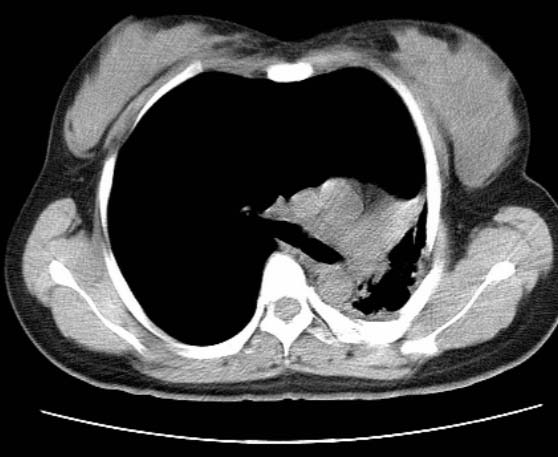

标题: CT25648:求教:是肺发育不全还是结核?

女  20岁。一月前咳血,诊“肺结核”抗痨治疗一月后,咳血停止,现复查。病人精神好。前后ct片对比未见明显变化。既往体检“正常”

1)考虑左肺结核并肺不张、支气管扩张。2)纵隔疝。

考虑左肺结核,左肺毁损,纵膈左偏,既往体检正常不可靠,tb一个月也不会这个样子的,有钙化,应该病程较长,冰冻三尺非一日之寒!

左肺发育不全。

考虑左肺结核,左肺毁损,纵膈左偏,既往体检正常不可靠,tb一个月也不会这个样子的,有钙化,应该病程较长,冰冻三尺非一日之寒

结核,左肺毁损。